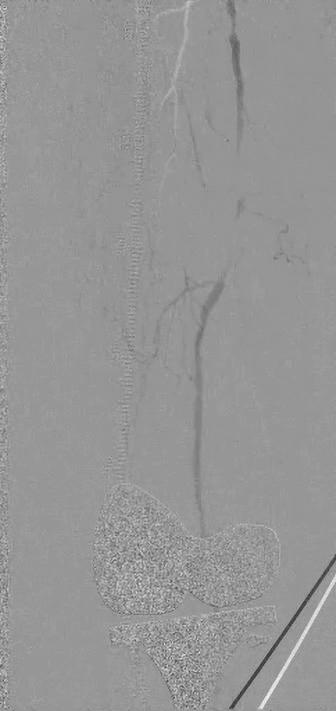

Embolization is often not very familiar to vascular surgeons. With the exception of type II endoleaks, these cases often get referred to interventional radiology (IR). As a result, there is little—if any—exposure to these procedures in vascular training. Once in practice, we don’t really think about them, despite the fact that they fit nicely into an outpatient practice.

At the hospital my practice covers, there is not much of an IR presence, so vascular surgery provides the emergency embolization services. Between the cold legs and ruptured aneurysms, we are also handling the gastrointestinal bleeds, ruptured spleens and postpartum hemorrhages. This has resulted in increasing comfort with these procedures. The anatomy and technical details are not dissimilar to what we do on a daily basis.

In addition to the hospital practice, we also have a busy office-based lab (OBL). In the context of this setting, we were asked by a gynecologist in the area about providing uterine artery embolization (UAE) for fibroids. Given our exposure to embolization procedures in the inpatient setting for emergencies, this felt like a very reasonable extension of our outpatient practice.

UAE has several characteristics that make it an ideal procedure for the outpatient setting. It is purely elective, which makes it practical to schedule. The patients are generally younger and lower risk than the typical vascular patient. The procedure itself is also low risk, with only relatively small sheaths required and the option for radial access. UAE also tends to be fairly routine and predictable. In a

involve gaining familiarity with the branch anatomy of the internal iliac artery and with embolization agents. In UAE, microparticles or liquid agents are often used. Comfort with radial access— less often used in vascular procedures— is helpful. Finally, relationships with gynecologists need to be developed, as they make these treatment decisions and referrals.

There are other elective embolization procedures that can be explored. While we’ve had minimal experience with it, prostate artery embolization is also well suited to the outpatient setting. Geniculate artery embolization is a newer procedure that has shown promise for patients with osteoarthritis who are not surgical candidates. Overall, when done well and with input from the relevant specialists, these are excellent procedures to expand an outpatient vascular practice.